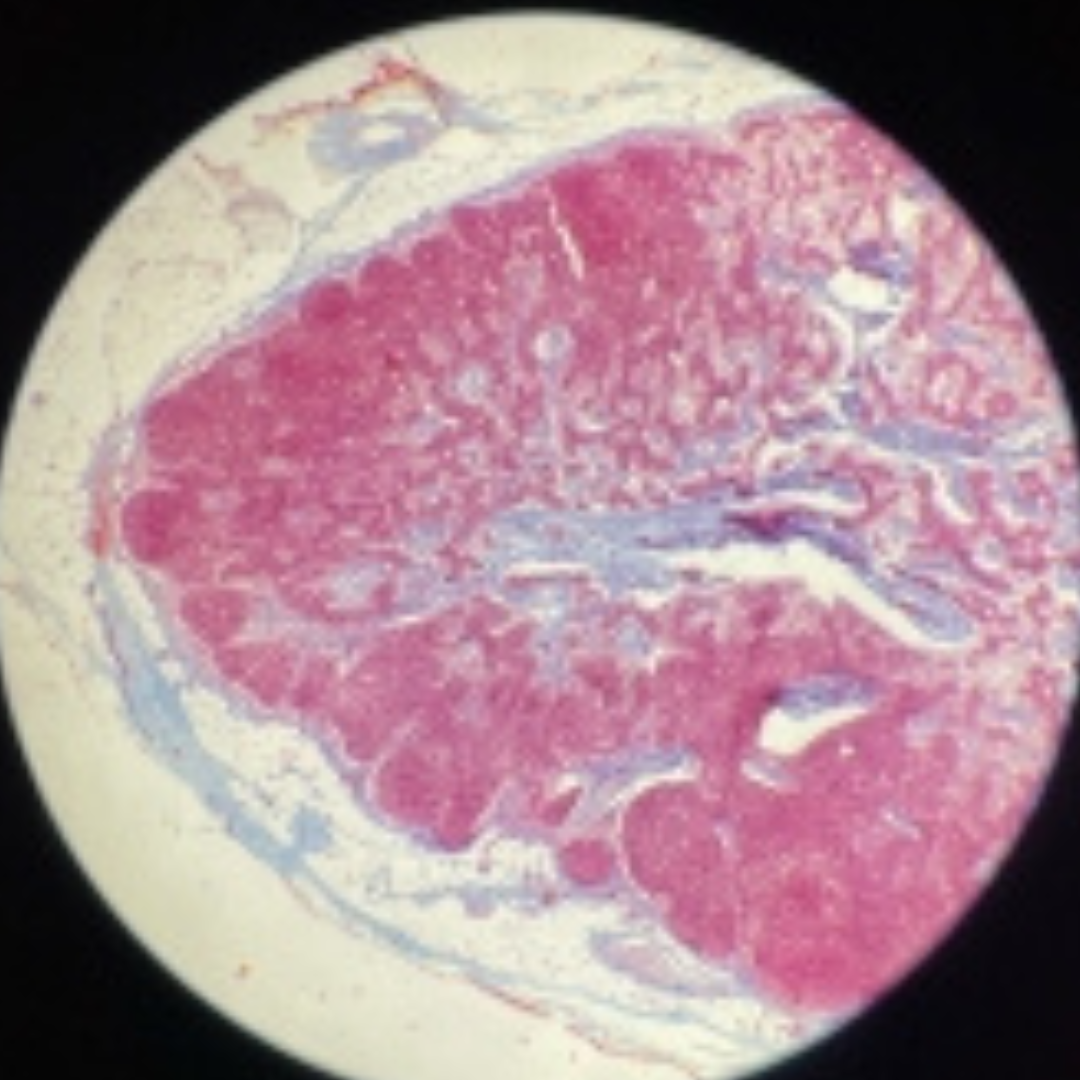

16

New cards

Tonsil

17

New cards

Tonsil

18

New cards

Tonsil

19

New cards

Tonsil